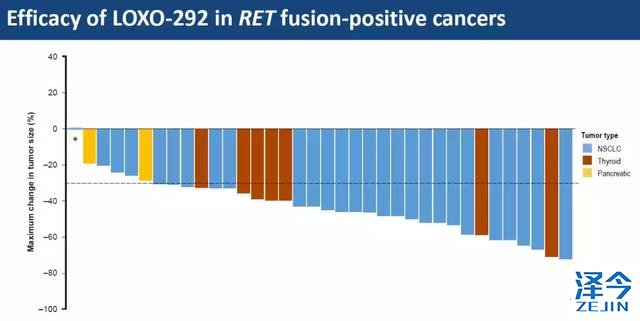

每个柱子代表一位患者,一共36位患者,包括27位非小细胞肺癌(蓝色)、7位甲状腺癌(红色)和2位胰腺癌(黄色),都有RET基因融合;柱子向下代表肿瘤缩小,可以看到除了第一根柱子,其余35根都是朝下的,代表着几乎所有的肿瘤都在缩小。